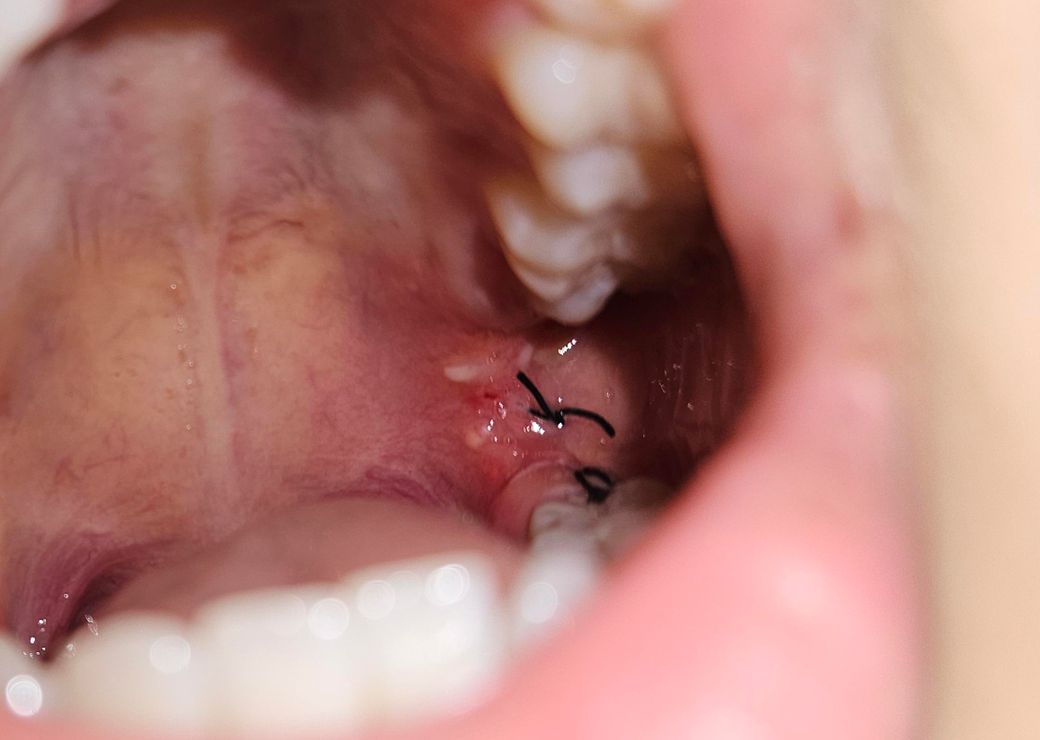

하얀뭐가 많이 올라왔는데ㅠ 상관없나요

이번에 사랑니가 완전매복이라 시간도 오래걸렸고 뼈삭제도 엄청 하셨다고ㅠㅠ

하얀건 딱히 신경안써도 되나요?

사진 상으로는 염증 등의 문제는 없어보입니다. 잘 낫고 있는 것 같으니 너무 걱정안하셔도 됩니다.

정상적으로 아물고 있는 것으로 보입니다. 하얀것은 주변 잇몸에 딱지 앉은 것으로 보면 됩니다.

사랑니 발치를 할떄 잇몸이 눌려서 생긴거같습니다. 큰 문제가 잇는건 아니니 너무 걱정하지마세요.

하얀건 단순 염증으로 보이는데 크게 신경쓰진 않아도 될 것 같습니다.